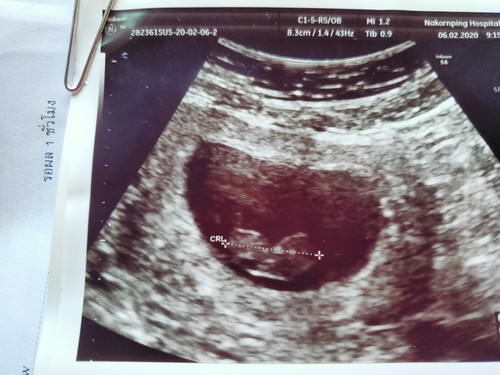

#บันทึกความจำอันแสนเจ็บปวด 06/02/2563 วันนี้หมอตรวจพบว่าหนูไม่มีหัวใจ แม่เกิดภาวะแท้ง หมอให้แม่ยุติการตั้งครรภ์นอนโรงพยาบาลวันนี้ แต่อาจารย์หมอท่านหนึ่งบอกว่า ผลอัลตร้าซาวด์ตั้งแต่แรกตอนเป็นก้อนเนื้อหนูมีหัวใจและสามารถโตได้ถึงวันนี้ เดือนที่แล้วหนูมีการเต้นของหัวใจ อาจารย์หมอขอให้รอปาฎิหารย์อีกสักครั้ง 11กุมภาพันธ์นี้ ถ้าหนูไหวหนูสู้กับแม่นะ ถ้าไม่ไหวไม่เป็นไร ครั้งหน้ามาเป็นลูกแม่อีกนะ แม่สัญญาจะดูแลหนูให้ดีกว่านี้ รักหนูมาก #น้องพอเพียง ????